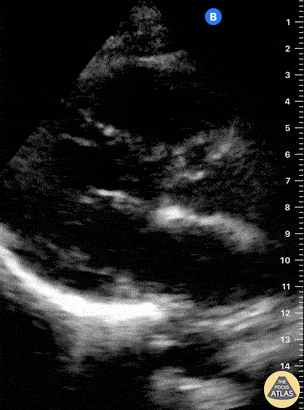

Normal Cardiac Anatomy - Normal PLAX

This is a normal parasternal long axis (PLAX) view. The right ventricle (RV) is at the top of the screen. Further down and from left to right: left ventricle (LV), outflow tract, aortic valve, ascending aorta. The actively moving mitral valve separates the LV from the left atrium (LA). At the bottom of the screen, the circular, anechoic image is the descending aorta. Dr. Felipe Urriola. Puerto Aysen Hospital Emergency Department, Chilean Patagonia.